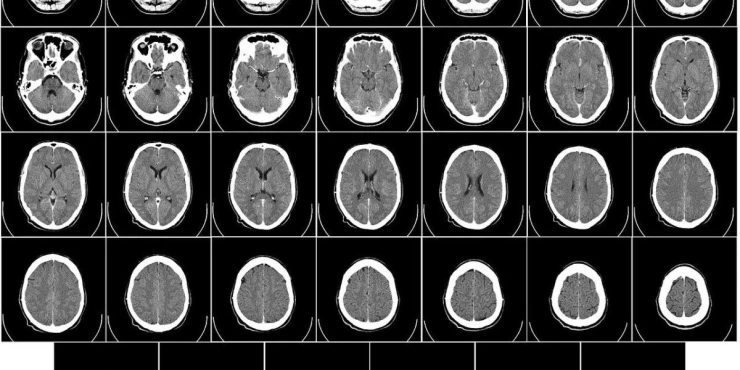

МНР на нејзиниот мозок откри абнормалности за кои е потребна операција. Лекарите утврдиле дека станува збор за видот Ophidascaris robertsi, а црвениот паразит можел да биде таму и до два месеци.